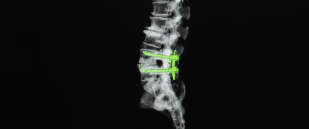

سماحة وجه فراس تخفي قهرا تذرفه شفاهه المرتجفة أثناء طلبه بعفة المساعدة والعون في معاناته بانزلاق غضروفي قطني في الفقرة ...

-

مريض شاب يعاني من مرض بالعمود الفقري بحاجة علاج

المريض ( م . ع . د ) يعاني من تيبس بالعمود الفقري

ونشاط بالمفاصل والتهاب بالعيون

وهو غير مستجيب للعلاج الدوائي

وبحاجة الى ... -

مريض اجرى عملية استئصال غضروف قطني بين الفقرة الرابعة والخامسة وبحاجة الى علاج فيزيائي

ه.ب.خ مريض اجرى عملية استئصال غضروف قطني بين الفقرة الرابعة والخامسة وبحاجة الى دواء ومتابعة علاج فيزيائي

يحتاج ... -